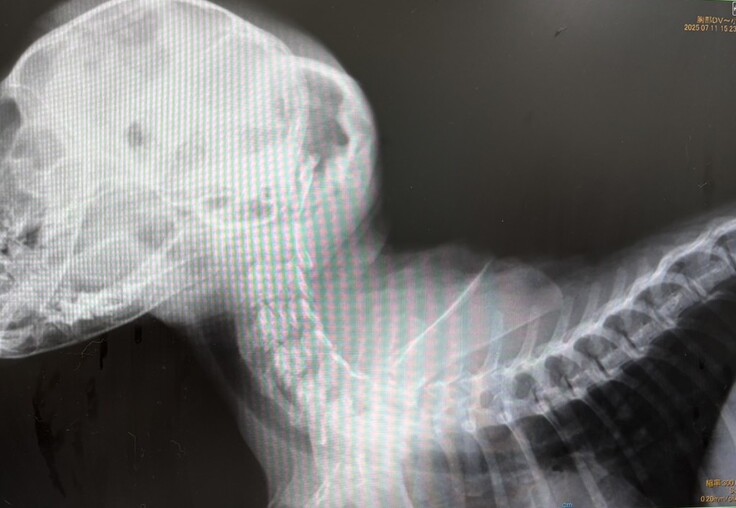

事故で瀕死だった朝顔ちゃん 7月

7月10日、ガリガリにやせ細った茶トラの女の子(生後3か月)が倉敷市保健所に収容されました。首は大きく曲がり、手足に力が入りません。後頭部の皮下には大きな血のかたまりがありました。このまま保健所に置いては死を待つばかり・・・。メンバーがかかりつけ医に走り、即日入院となり、点滴と投薬治療が始まりました。

入院して5日目の7月14日、手足を動かしたり、自分で移動をしたりと動きが見られるようになりました。名前を呼ぶと返事もします。

7月22日、状態が安定したため、後はリハビリをとの判断で退院となりました。

首は相変わらず曲がったままで自分で支えることはできません。手足に力も入りません。食事や排せつには全面的な介護が必要でした。

お世話をしてくれる預かりさんの献身的な介護と、頼もしいリハビリ仲間の登場で、朝顔ちゃんはたくさんの奇跡を見せてくれました。(次編に続く)